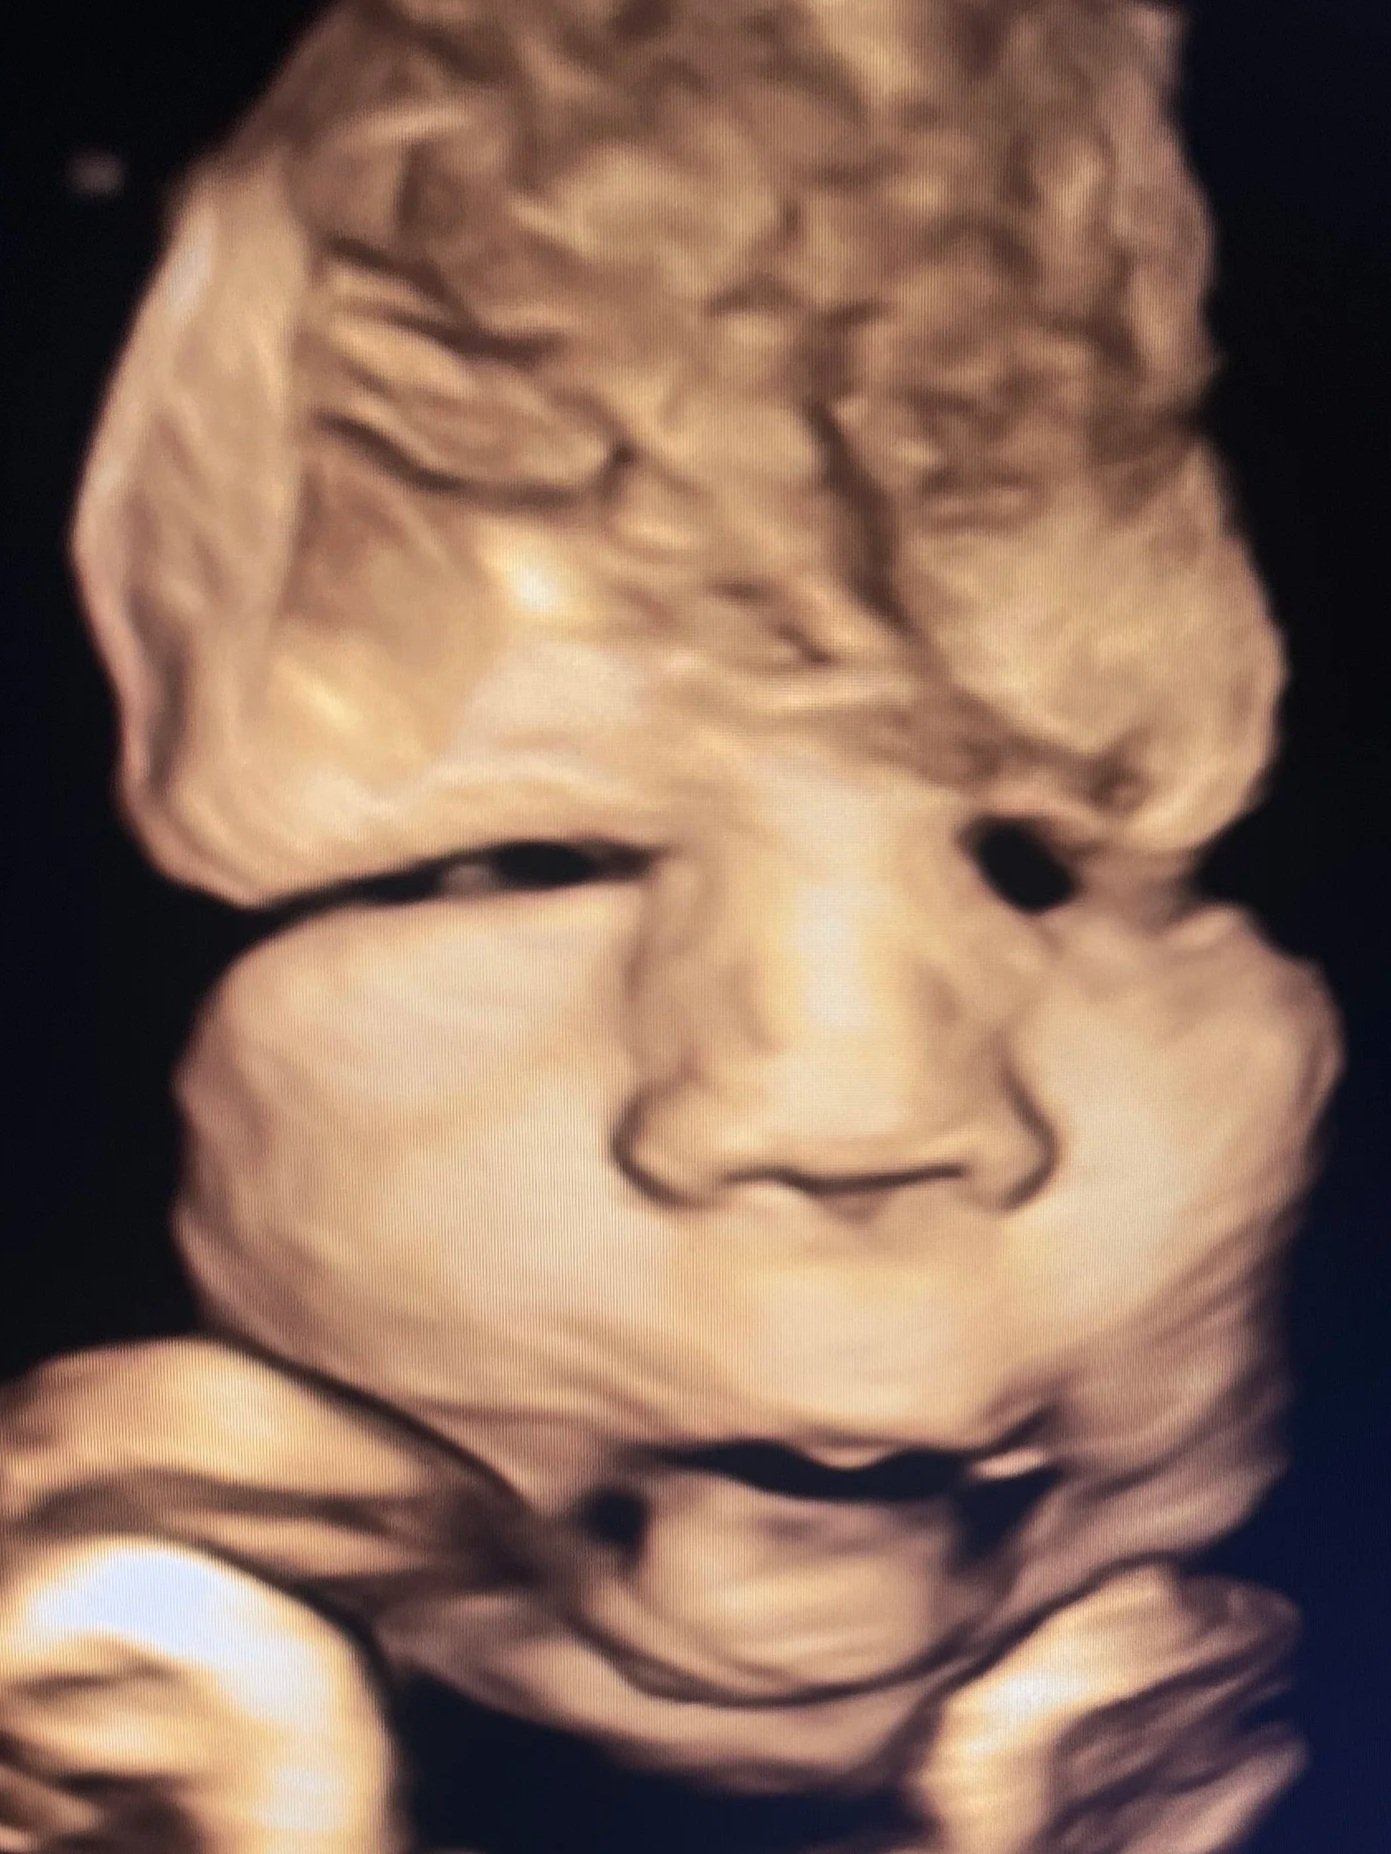

The Baby Gallery